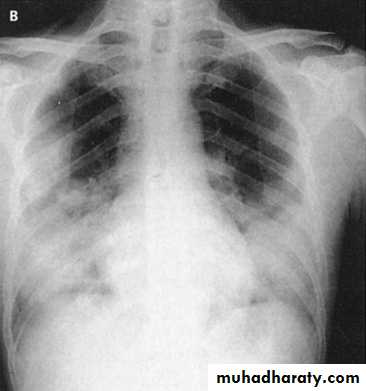

Chest x-rays of a 46-year-old man with SARS. The left lower lung infiltrate seen initially (A) progressed to multiple bilateral opacities (B).